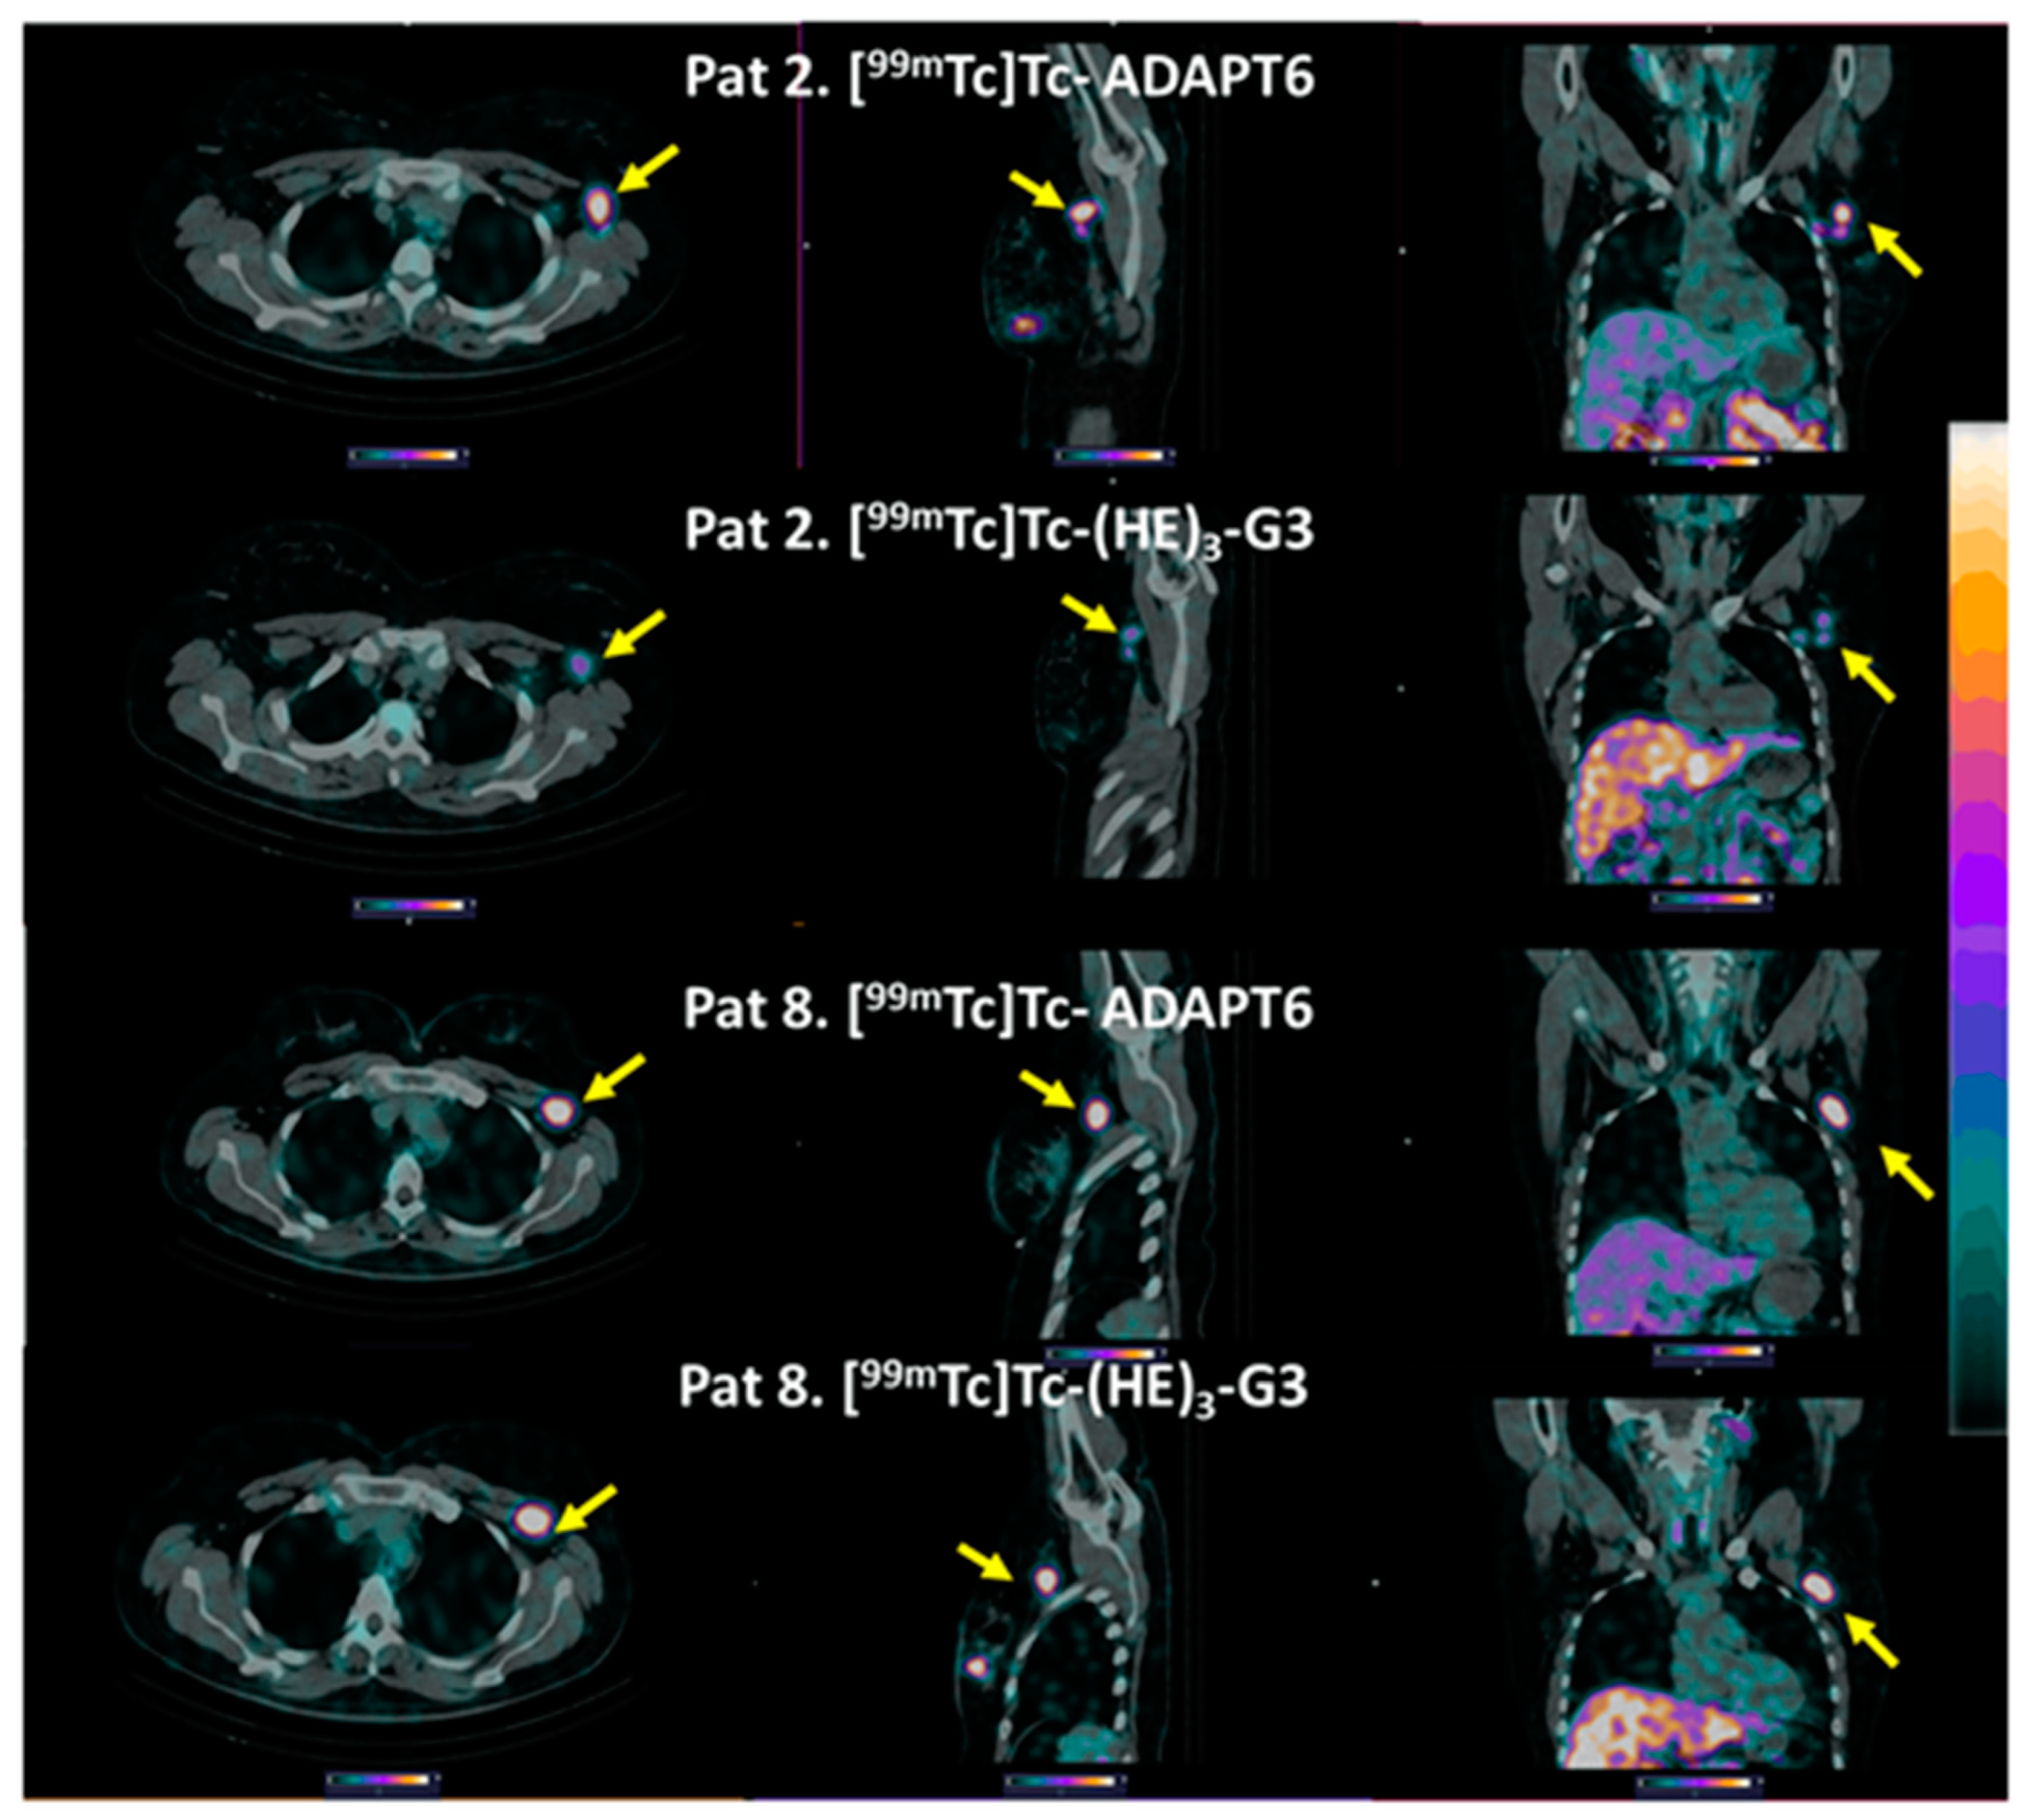

3. Results

4. Discussion